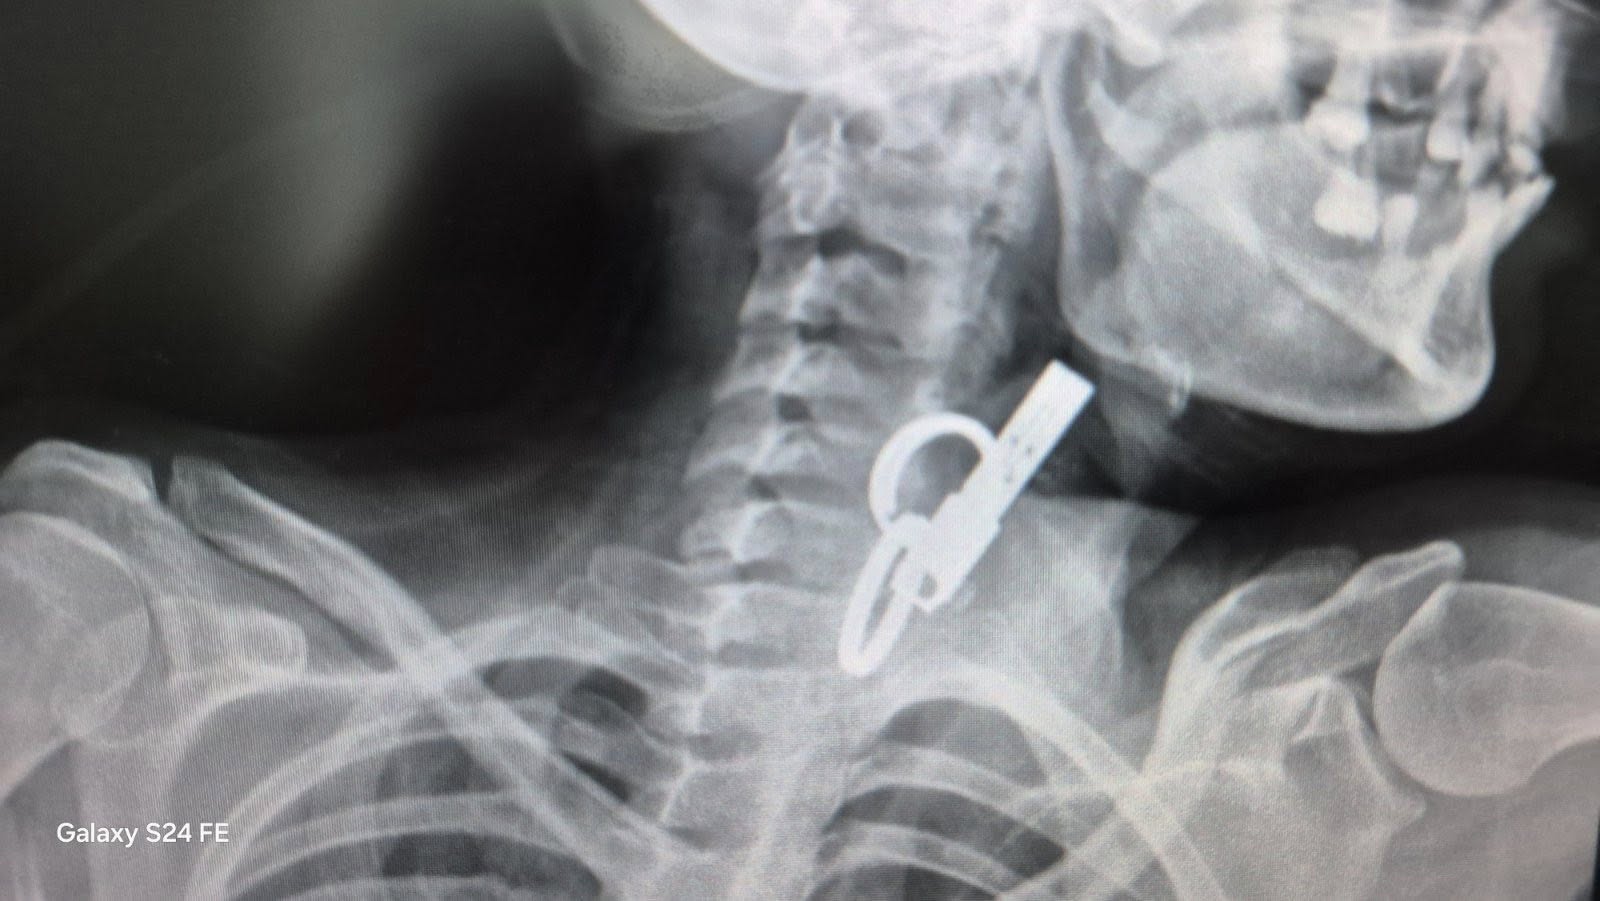

На Тернопільщині 40-річна жінка проковтнула ключ, щоб не віддати його родичам. Про це повідомили у Гусятинській комунальній лікарні та Zahid.net, пише ПІК.

Жінка близько тиждень прожила із ключем у стравоході. За словами родичів, їй було зле, вона не могла їсти.

Команда медиків провели ендоскопічне видалення великого ключа зі стравоходу без виконання хірургічного розрізу.

Стан пацієнта після втручання стабільний, самопочуття задовільне. Після перебування у відділенні анестезіології та інтенсивної терапії її перевели до загальнохірургічного відділення для подальшого лікування та медичного спостереження.